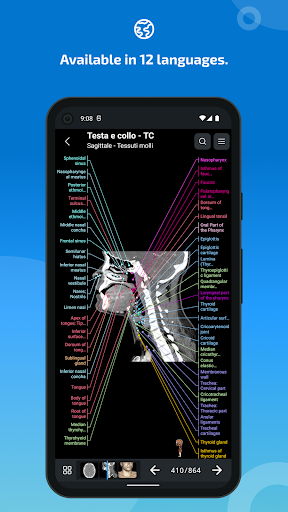

لغة جديدة: الإيطالية

- وحدة جديدة للمشتركين: التشريح الشعاعي للعمود الفقري العنقي في التصوير بالرنين المغناطيسي ، واستكشاف الأجزاء المحورية والسهميّة والإكليلية